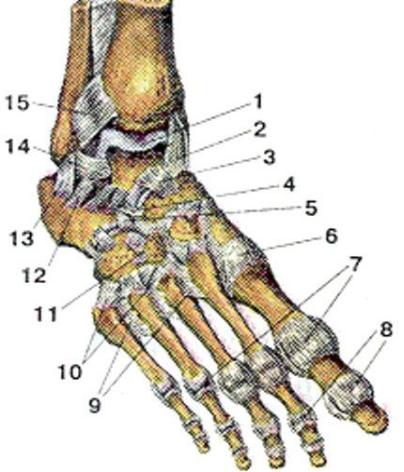

Анатомические фото голеностопного сустава и его суставных поверхностей